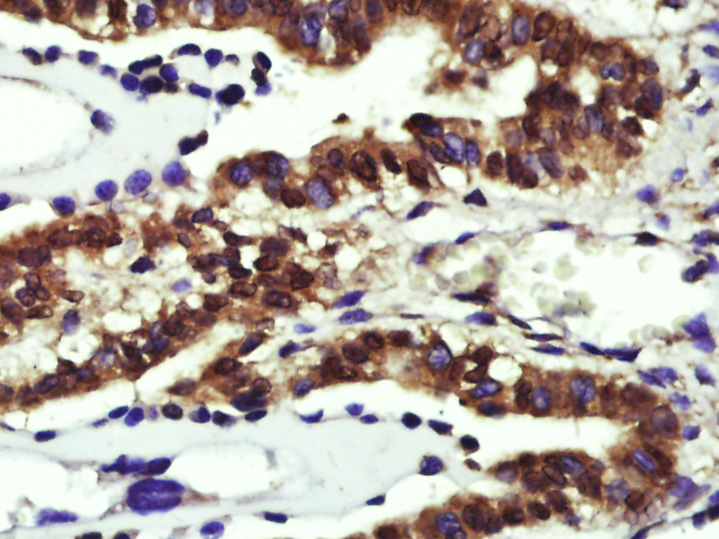

產(chǎn)品圖片

Paraformaldehyde-fixed, paraffin embedded (Rat liver); Antigen retrieval by boiling in sodium citrate buffer (pH6.0) for 15min; Block endogenous peroxidase by 3% hydrogen peroxide for 20 minutes; Blocking buffer (normal goat serum) at 37°C for 30min; Antibody incubation with (Cyclin D1) Polyclonal Antibody, Unconjugated (bs-20596R) at 1:500 overnight at 4°C, followed by a conjugated secondary (sp-0023) for 20 minutes and DAB staining.

Paraformaldehyde-fixed, paraffin embedded (Mouse brain); Antigen retrieval by boiling in sodium citrate buffer (pH6.0) for 15min; Block endogenous peroxidase by 3% hydrogen peroxide for 20 minutes; Blocking buffer (normal goat serum) at 37°C for 30min; Antibody incubation with (Cyclin D1) Polyclonal Antibody, Unconjugated (bs-20596R) at 1:400 overnight at 4°C, followed by operating according to SP Kit(Rabbit) (sp-0023) instructionsand DAB staining.

Paraformaldehyde-fixed, paraffin embedded (Mouse placenta); Antigen retrieval by boiling in sodium citrate buffer (pH6.0) for 15min; Block endogenous peroxidase by 3% hydrogen peroxide for 20 minutes; Blocking buffer (normal goat serum) at 37°C for 30min; Antibody incubation with (Cyclin D1) Polyclonal Antibody, Unconjugated (bs-20596R) at 1:400 overnight at 4°C, followed by operating according to SP Kit(Rabbit) (sp-0023) instructionsand DAB staining.

Paraformaldehyde-fixed, paraffin embedded (mouse liver); Antigen retrieval by boiling in sodium citrate buffer (pH6.0) for 15min; Block endogenous peroxidase by 3% hydrogen peroxide for 20 minutes; Blocking buffer (normal goat serum) at 37°C for 30min; Antibody incubation with (Cyclin D1) Polyclonal Antibody, Unconjugated (bs-20596R) at 1:200 overnight at 4°C, followed by operating according to SP Kit(Rabbit) (sp-0023) instructionsand DAB staining.

Paraformaldehyde-fixed, paraffin embedded (rat liver); Antigen retrieval by boiling in sodium citrate buffer (pH6.0) for 15min; Block endogenous peroxidase by 3% hydrogen peroxide for 20 minutes; Blocking buffer (normal goat serum) at 37°C for 30min; Antibody incubation with (Cyclin D1) Polyclonal Antibody, Unconjugated (bs-20596R) at 1:200 overnight at 4°C, followed by operating according to SP Kit(Rabbit) (sp-0023) instructionsand DAB staining.

Paraformaldehyde-fixed, paraffin embedded (rat kidney); Antigen retrieval by boiling in sodium citrate buffer (pH6.0) for 15min; Block endogenous peroxidase by 3% hydrogen peroxide for 20 minutes; Blocking buffer (normal goat serum) at 37°C for 30min; Antibody incubation with (Cyclin D1) Polyclonal Antibody, Unconjugated (bs-20596R) at 1:200 overnight at 4°C, followed by operating according to SP Kit(Rabbit) (sp-0023) instructionsand DAB staining.

Paraformaldehyde-fixed, paraffin embedded (mouse kidney); Antigen retrieval by boiling in sodium citrate buffer (pH6.0) for 15min; Block endogenous peroxidase by 3% hydrogen peroxide for 20 minutes; Blocking buffer (normal goat serum) at 37°C for 30min; Antibody incubation with (Cyclin D1) Polyclonal Antibody, Unconjugated (bs-20596R) at 1:200 overnight at 4°C, followed by operating according to SP Kit(Rabbit) (sp-0023) instructionsand DAB staining.

Paraformaldehyde-fixed, paraffin embedded (rat uterus); Antigen retrieval by boiling in sodium citrate buffer (pH6.0) for 15min; Block endogenous peroxidase by 3% hydrogen peroxide for 20 minutes; Blocking buffer (normal goat serum) at 37°C for 30min; Antibody incubation with (Cyclin D1) Polyclonal Antibody, Unconjugated (bs-20596R) at 1:200 overnight at 4°C, followed by operating according to SP Kit(Rabbit) (sp-0023) instructionsand DAB staining.